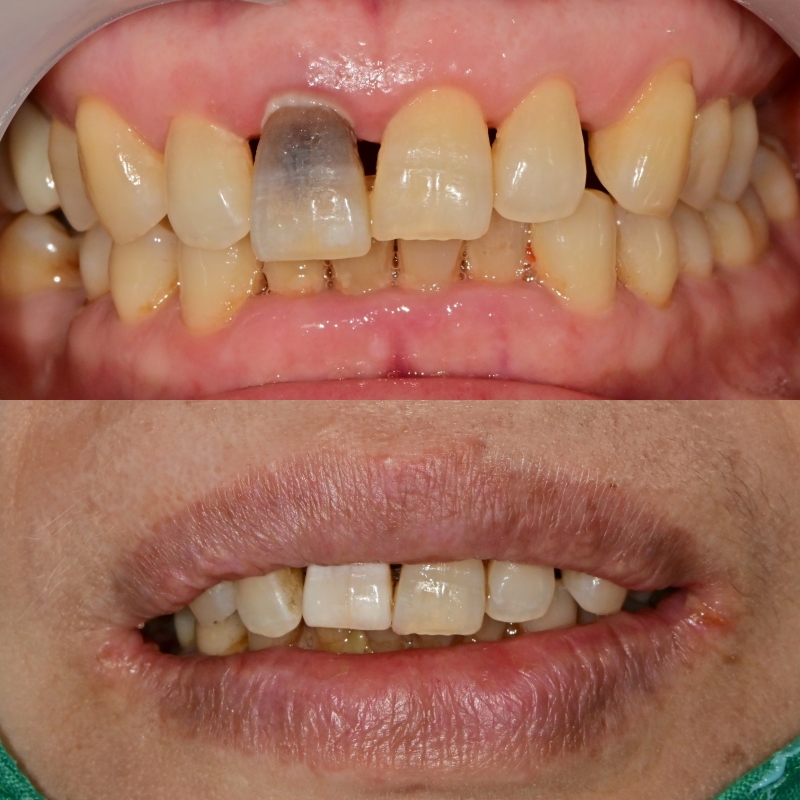

기존 치아를 이용하여 빈 공간 회복

초진 사진에는 기존 치아가 신경치료가 되어 있지만 오랜 시간에 의해 내부가 변색되어 치아가 어둡게 보이는 상태로 지내 오셨습니다.

큰 불편감 없이 지내시다 최근 해당 치아가 치주가 더 안 좋아져서 흔들림을 불편감으로 내원해 주셨습니다.

이미 치아의 동요도가 심해졌기 때문에 해당 부위는 발치 후 임플란트가 필요했습니다.

수술은 통법대로 간단하게 진행하고 맨 앞의 대문니가 없는 상태보다 임시적으로 회복하는 것이 심미적으로 좋다는 판단하에 발치한 치아를 이용하여 빈 공간에 붙여드리기로 했습니다.

기존 발치한 치아를 다듬는 과정에서 신경치료되어 변색된 부위를 다듬었더니 미백을 한 것처럼 임시치아가 환해진 것을 볼 수 있습니다.